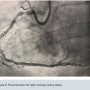

Access was obtained via the right common femoral artery. The initial lesion in the mid proximal RCA can be seen in Figure 2. An 8 French (Fr) long Destination sheath (Terumo) was used for maximum support, and a 0.75 Amplatz left (AL) 2 Guide catheter (Boston Scientific) was used for access support and assistance. A Balance Middleweight (BMW) wire (Abbott Vascular) was initially used to advance the catheter into the target artery. We switched to a 300 cm PT choice wire (Boston Scientific) in an attempt to cross the existing stent lumen, with the use of a 6 Fr Guideliner (Teleflex) for additional support. A 2.5 mm x 12 mm balloon (Medtronic) failed to cross the mid RCA stent fracture and ISR. The two markers on the balloon created a too-large catheter diameter, so a 1.25 mm x 12 mm single marker balloon (Medtronic) was chosen instead and successfully crossed. The balloon was inflated to 20 atmospheres (atm) and removed. A second attempt to pass the original 2.5 mm x 12 mm balloon (Medtronic) once again failed. The ELCA catheter was positioned just proximal to the mid RCA ISR within the fractured stent lumen. We started with an 0.9 laser catheter with the tip terminating just proximal to the ISR. An initial fluence of 45 mJ/mm2 was applied and gradually increased to a fluence of 80 mJ/mm2 for a total of almost 5 minutes while the tip was still positioned proximally to the ISR. The laser then was able to advance through the obstruction and was removed. Over the wire, a 2.5 mm x 12 mm balloon was inflated up to 20 atm for 25 seconds and then replaced with a 3.0 mm x 20 mm balloon (Medtronic) inflated to nominal pressure. The same 3.0 mm balloon was used at the very proximal aspect of the ISR as a pre-dilation before two drug-eluting stents (DES) were placed: a 3.0 mm x 18 mm Onyx DES (Medtronic) at the mid RCA and a second 3.0 mm x 30 mm Onyx DES at the proximal to mid RCA. The 3.0 mm x 18 mm Onyx DES stent was deployed at 22 atm for 15 seconds and the 3.0 mm x 30 mm Onyx DES was deployed 20 atm for 10 seconds. Post stent deployment, angiography clearly demonstrated reduction of the stenosis from approximately 99% to <10% at the site of the original stenosis in the proximal to mid RCA. At the end of the procedure, Thrombolysis In Myocardial Infarction (TIMI)-III flow was achieved (Figure 3). Inline flow was successfully restored across the entire RCA. The procedure was uncomplicated, but required the use of significant amounts of contrast (500 mL) and fluoroscopy (81.1 minutes). The patient was discharged the following day without incident, and has thus far remained asymptomatic throughout his follow-up with his referring cardiologist.